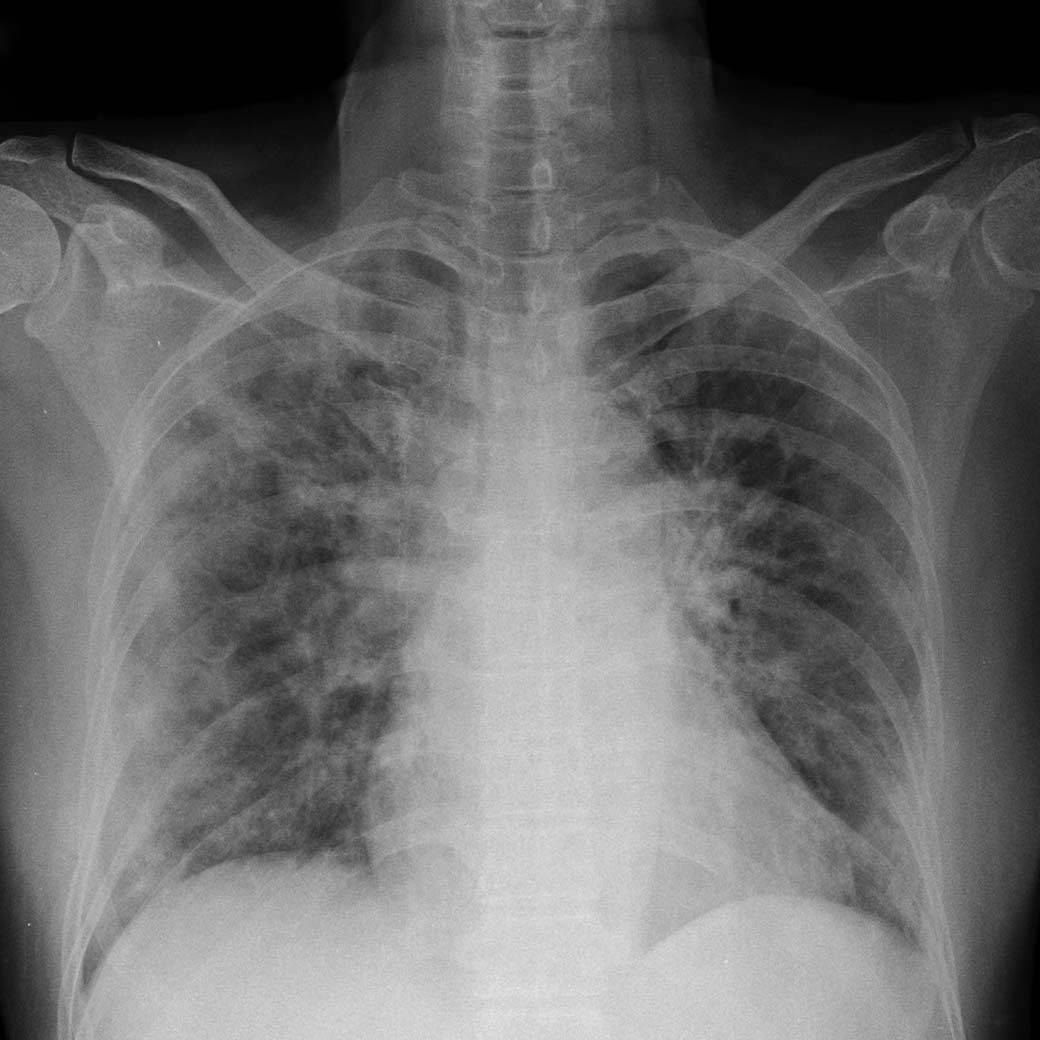

A machine learning model developed at Princeton scanned dozens of simple chest X-rays and predicted the type and severity of a patient's lung damage. Two types of COVID-19 lung damage are shown here in clusters, labeled COVID-19 H (blue) for patients likely needing a ventilator, and COVID-19 L (black) for patients who may need less invasive treatments. The model was also able to differentiate patients with normal lungs (red) and lungs damaged from non-COVID pneumonia (green).

While current differentiation methods involve expensive and time-consuming procedures, such as computed tomography (CT) scans, Fleischer's machine learning model looks at a simple X-ray image and finds patterns that are too subtle even for the expert human eye. This tool would give doctors a new measure for determining the type and severity of COVID-19 pneumonia. And the process, on the ground, is simple.

The work is based on a medical article by Dr. Luciano Gattinoni, who described the two conditions. Many COVID-19 cases show a familiar form of pneumonia, where the tiny sacs lining a patient's lungs are stiff and heavy with fluid. The stiffness restricts breathing and prevents oxygen transfer to the bloodstream. Treatment for this form involves intubation with a mechanical ventilator, where a computerized machine controls the patient’s breathing. But more than half of the patients look more like an altitude-sick mountaineer: blood-oxygen levels are dangerously low, but the lungs work fairly well and breathing is nearly normal. Perversely, in these cases, mechanical ventilation can damage the lungs, exacerbating the disease. This second category demands a less invasive treatment under Dr. Gattinoni's system, such as low-pressure oxygen, repositioning of the body, and the use of a sleep apnea device.